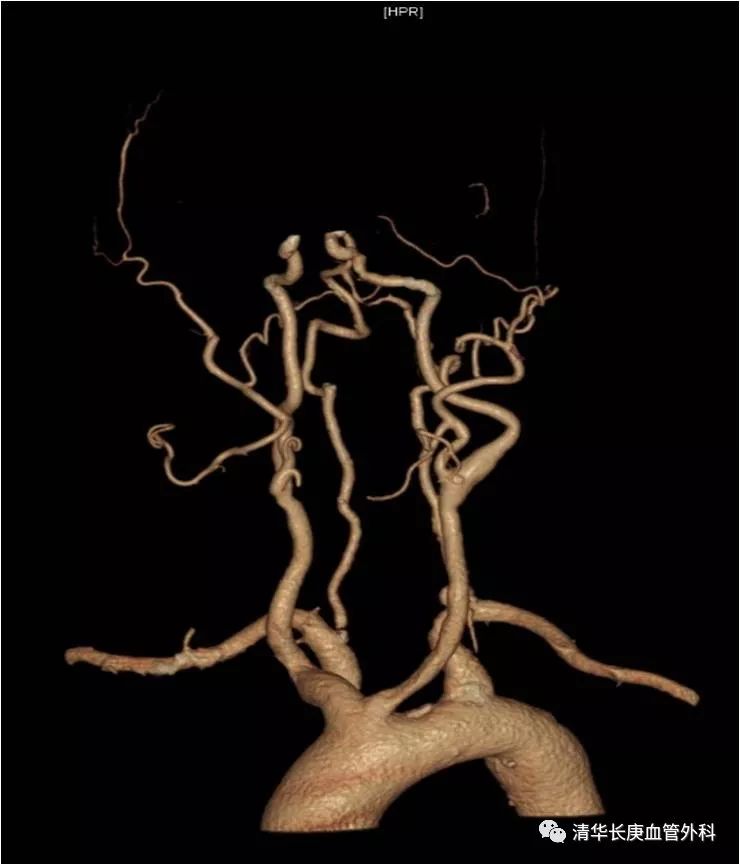

赵克强副主任医师,以典型病例录播形式,向学员们分享了弓上动脉病变的治疗,包括锁骨下动脉闭塞、复杂弓型颈动脉支架的入路建立、多发病变、串联病变的治疗策略,以及弓上病变围术期管理、术中技巧、常见并发症及预防措施;学员们积极踊跃、畅所欲言、沟通心得,对弓上病变的诊治有了进一步的认识、体会。

锁骨下动脉闭塞,长鞘+椎管+CXI+V18同轴系统通过病变

双导丝技术

不友好弓型的入路建立